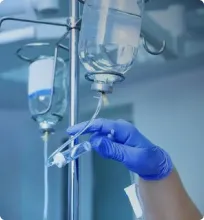

Лечение алкогольной деменции

Раннее лечение является ключом к успешному лечению деменции, связанной с алкоголем. При достаточно раннем обнаружении пациенты с более общим типом ОРЗ могут значительно улучшить свое состояние, отказавшись от алкоголя и придерживаясь сбалансированной диеты.

Своевременное лечение тиамином (витамином B1) людей с энцефалопатией Вернике потенциально может предотвратить или уменьшить развитие синдрома Вернике-Корсакова. Однако лечение витамином B1 редко улучшает потерю памяти, которая имеет место после развития корсаковского психоза.

Отказ от употребления алкоголя предотвратит дополнительную потерю функции мозга и его повреждение. Также может помочь улучшение диеты пациента. Однако диета не заменяет воздержание от алкоголя в предотвращении ухудшения деменции, связанной с алкоголем.